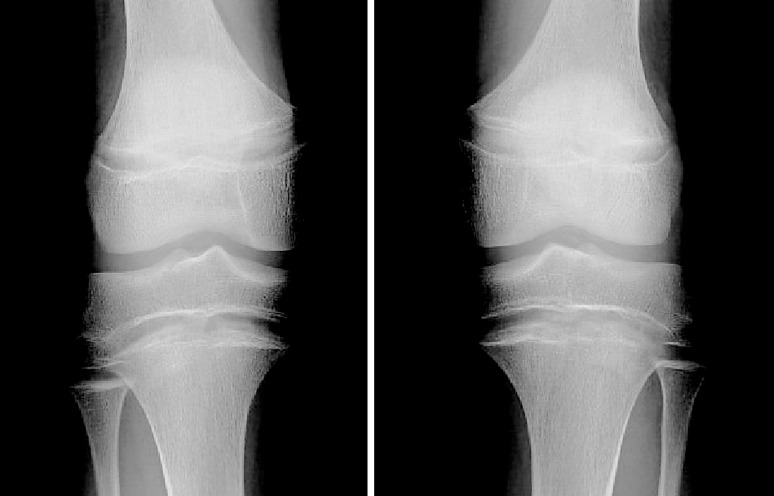

Case presentation: A 13-year-old boy with ADHR with the appearance of rickets on bone radiographs as well as documented hypophosphatemia was found to have a novel S180I variant in the FGF23 gene. Unlike previously reported pathogenic variants, this novel variant was located outside the RXXR motif. Subsequently, Western blotting showed that the S180I mutant was resistant to proteolysis than the wildtype, similar to pathogenic variant model mutant (R176Q/R179Q).